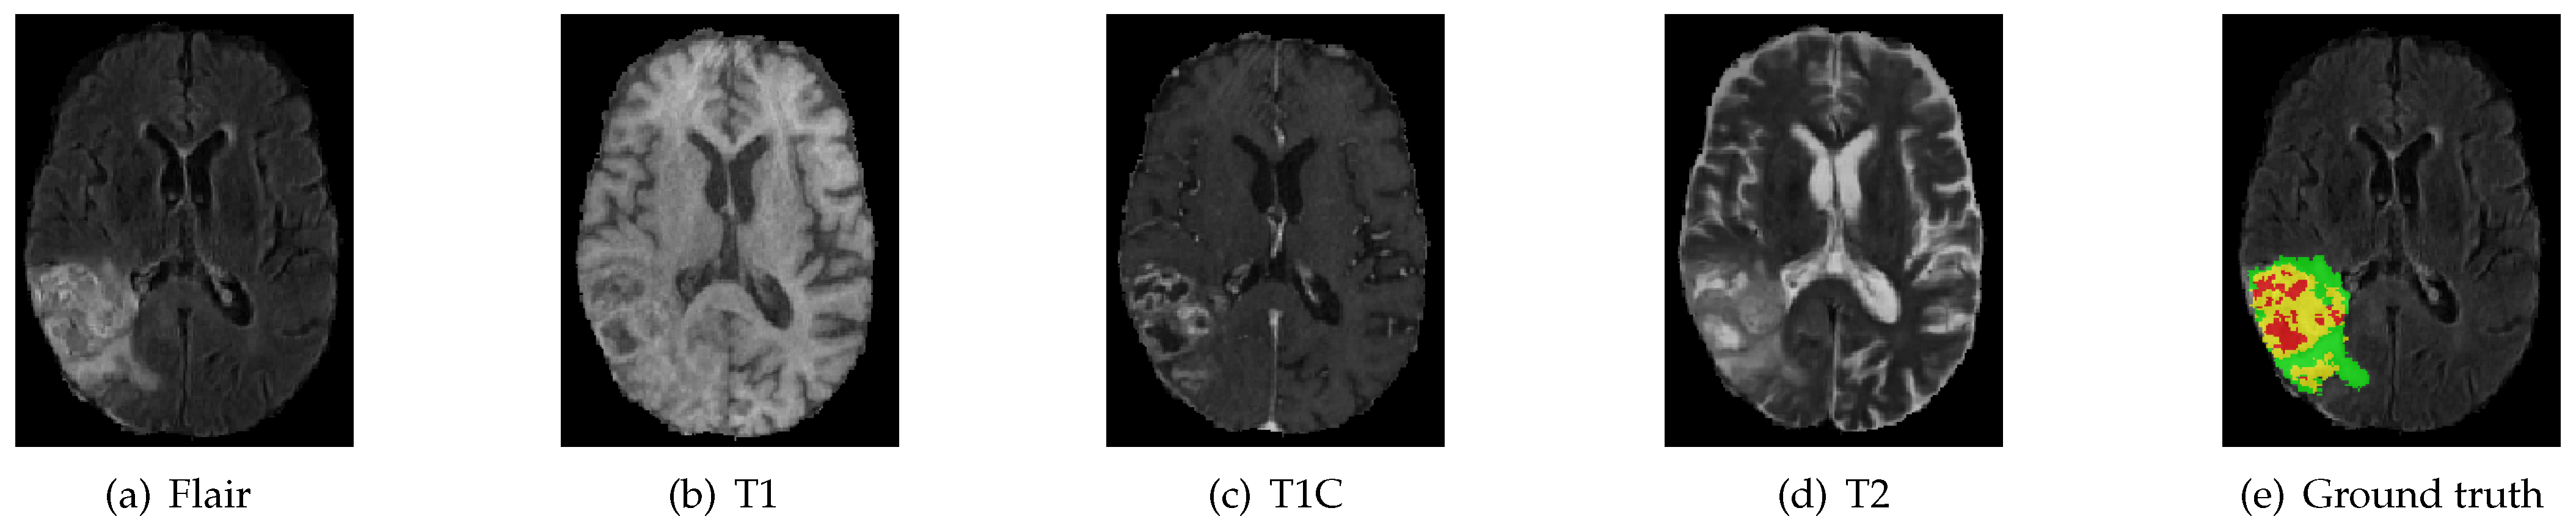

4.1. Benchmark Dataset and Evaluation Criteria